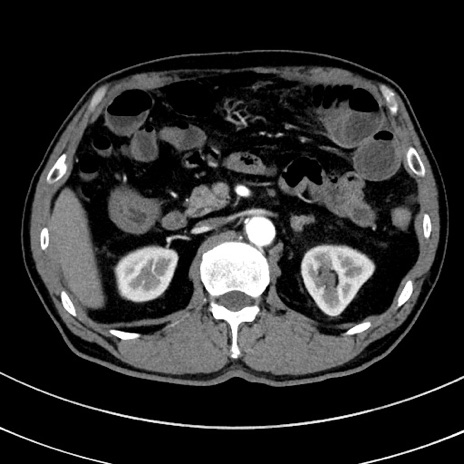

症例8(横断像)

【症例】 60歳代男性

【主訴】 黒色吐物

【現病歴】 4日前から嘔気自覚、2日前の朝食後にも嘔気あり、自分で手で嘔吐反射起こし嘔吐したところ血が混ざっていたため受診。

【既往歴】 5年前汎発性腹膜炎を伴う急性虫垂炎で手術、高血圧、前立腺肥大症、高脂血症

【身体所見】 腹部正中に手術癩痕あり 腹部平坦・軟圧痛なし膨満感あり

【データ】WBC 8400、CRP 4.54